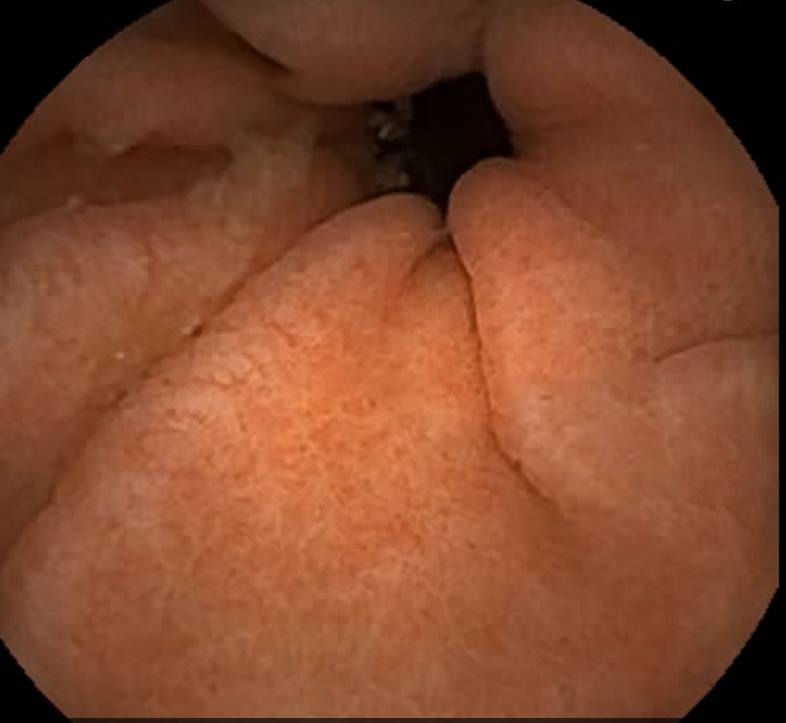

Capsule Endoscopy: A Normal Pylorus